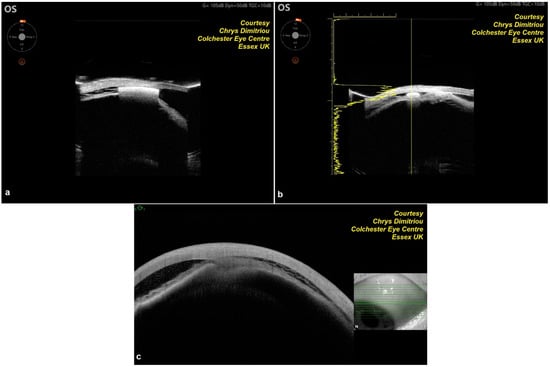

Figure 3. Anterior segment optical coherence tomography sections of MINIject showing a reservoir—supraciliary “bleb”.

The MINIject implant is an innovative, preloaded, ab interno MIGS device specifically designed to improve aqueous humor outflow by directing it into the supraciliary space. Measuring 5 mm in length, the implant is constructed from medical-grade silicone, known as STAR material, which is designed to conform to the anatomical features of the supraciliary space. This material ensures that the device integrates effectively with the surrounding tissue for optimal performance. The MINIject has a unique porous design, which facilitates aqueous drainage through both the small cleft created during implantation and the porous structure of the implant itself. This dual-flow mechanism enhances the efficiency of the implant in reducing IOP. The device is preloaded into a delivery sheath, which is then connected to a delivery tool, making the implantation process straightforward and precise. This design ensures that the device can be accurately placed into the supraciliary space with minimal complication, contributing to its effectiveness as a MIGS option for glaucoma treatment (Figure 1 and Figure 2 illustrate the device and its placement mechanism).

The MINIject can be implanted either as a standalone procedure or at the end of cataract surgery. All patients received sub-Tenon’s anesthesia preoperatively, consisting of lignocaine 2% and hyaluronidase 150 IU/mL. A temporal 2.0–2.2 mm clear corneal incision was used. Miochol-E (Bausch & Lomb, Vaughan, ON, Canada) and a highly cohesive viscoelastic (Healon GV Pro, Johnson & Johnson Vision, Jacksonville, FL, USA) were injected to constrict the pupil, form the anterior chamber, and maintain stability. The patient’s head was tilted away from the surgeon as in most MIGS procedures, and a surgical gonioprism was used to visualize the angle. The implant was advanced in the supraciliary space until the green ring was positioned at the level of the scleral spur. This way, only 0.5 mm of the device was exposed in the anterior chamber, thus protecting against corneal endothelium damage (Figure 3 and Figure 4). At the end of the surgery, intracameral cefuroxime 1.0 mg/0.1 mL was given, and the standard postoperative regime included a combination of topical antibiotics and steroids, and, in the case of diabetic patients, a course of topical non-steroidal anti-inflammatory drugs (NSAIDs) was prescribed. All glaucoma medications were discontinued postoperatively, and they were introduced again as needed.